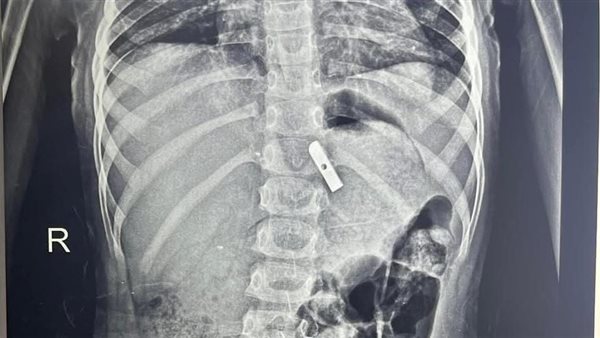

استخراج «موس براية» من معدة طفلة 7 سنوات في بنها